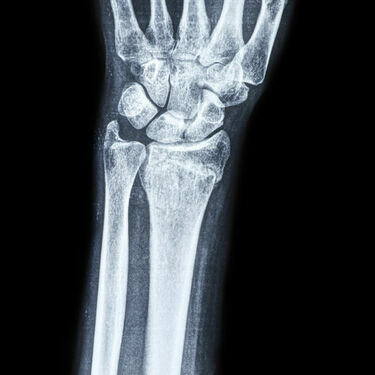

West Virginia’s Intermediate Court of Appeals upheld a 13% permanent partial disability award for a worker’s wrist injury.

Case: Murray American Energy Inc. v. Gasvoda, No. 25-ICA-78, 10/24/2025, published.

Facts: Joseph Gasvoda worked for Murray American Energy Inc. He injured his wrist at work in June 2019.

A claims administrator for Murray’s… Read more »Nov 7, 2025